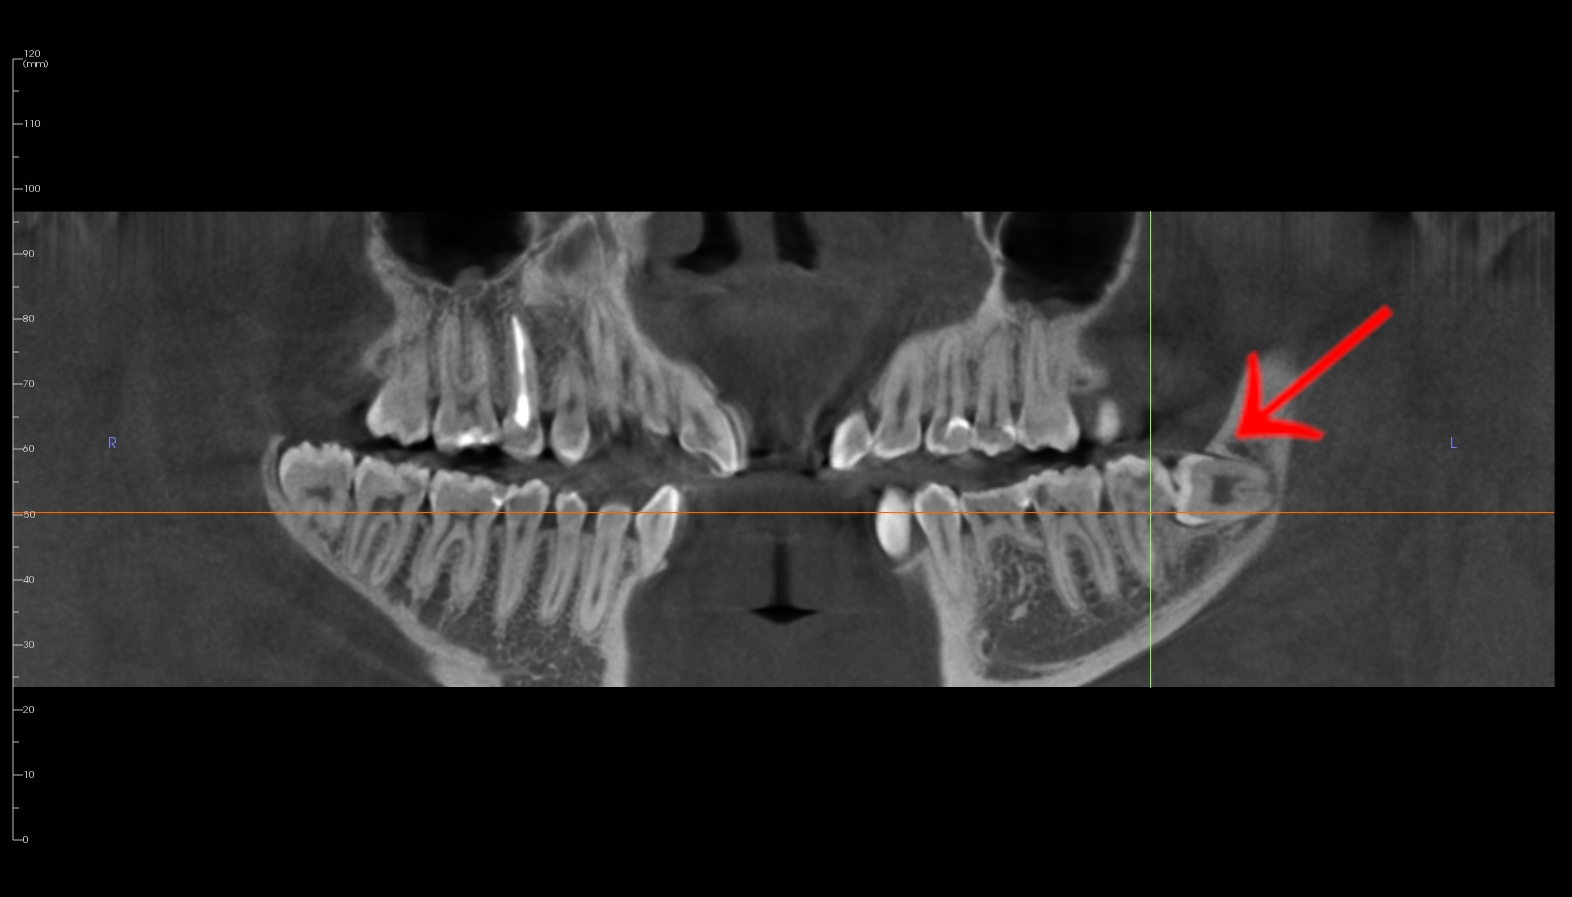

🦷 CASE STUDY: Usunięcie zatrzymanej ósemki w orientacji poziomej — historia pani Igi (20 lat)

Pani Iga zgłosiła się do naszego Instytutu z powodu zatrzymanej dolnej ósemki po lewej stronie, która — jak pokazało badanie tomograficzne — była ustawiona poziomo, głęboko w kości. Taka pozycja zęba uniemożliwia prawidłowe wyrżnięcie i może prowadzić do bólu, stanu zapalnego, a w przyszłości nawet do uszkodzeń sąsiednich zębów.